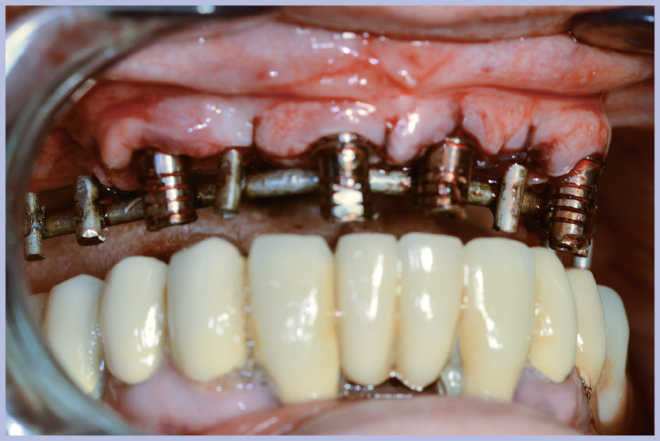

Sui monconi, dopo aver attivato la connessione a cono Morse (Fig. 3), sono state fissate le apposite cappette in titanio con le viti a testa alta (Fig. 4) ed è stata realizzata un’armatura di rinforzo per mezzo di una sincristallizzatrice intra-orale. In particolare la barra è stata ottenuta mediante saldatura sulle cappette di un filo pre-modellato di titanio grado 2 (Figg. 5, 6).

- Fig. 4 – Fissaggio delle cappette in titanio

- Figg. 5, 6 – Struttura di rinforzo ottenuta saldando intra-oralmente un filo di titanio alle cappette